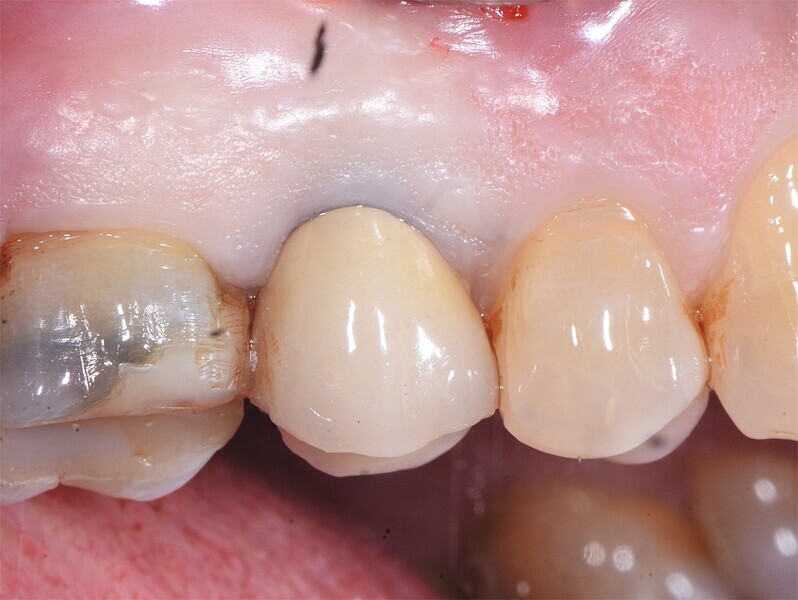

Un patient présentant un défaut infraosseux s’est présenté au cabinet dentaire avec le souhait explicite d’un traitement par un implant en zircone, pour remplacer l’une de ses molaires. Un implant deux pièces en zircone a donc été posé et le défaut infra-osseux a été traité dans le même temps, au moyen d’une allogreffe osseuse et du dérivé de matrice amélaire Emdogain (Straumann). La mise en charge n’a pas été réalisée à ce stade (Figs. 35–45).

Fig. 44 : Radiographie de contrôle et excellente intégration de l’implant en céramique dans l’environnement parodontal.

Fig. 45 : Radiographie de contrôle et excellente intégration de l’implant en céramique dans l’environnement parodontal.